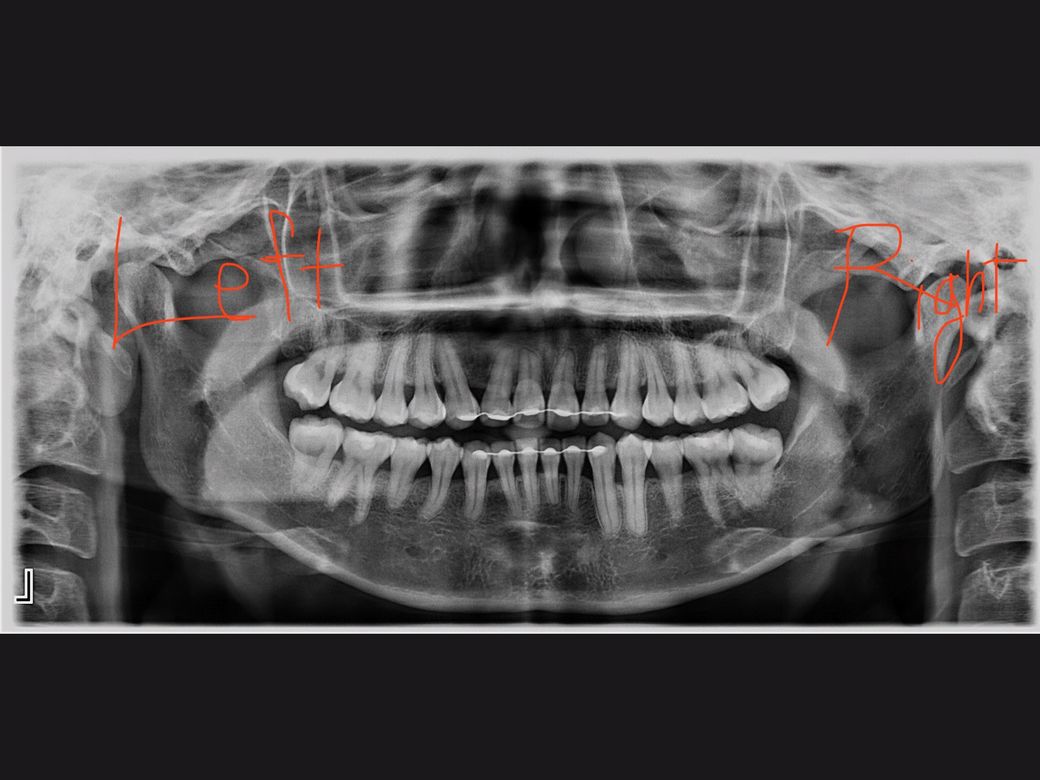

치아옆면 즉 협측면이라고 하며 협측면에 선상으로 생긴 표면충치 입니다, 이정도 충치는 치료하지 않고 그냥두면 것이 좋습니다. 더 진행 안될 가능성 높습니다.

엑스레이를 찍고 진찰 받았더니, 아무 이상 없다고 했다면 충치는 아닐 것으로 판단됩니다.

사진으로는 충치의 여부를 정확히 판단하기 힘들어 보입니다. 초기 충치의 경우에는 주변 치아보다 하얀색을 띄는 경우가 있습니다. 충치의 여부를 정확하게 확인하기 위해서는 치과에서 진료를 받아보는 것이 좋습니다.

사진의 화질이 별로 좋지 않기는 하지만 큰 문제는

없어보입니다. 육안으로 직접 확인하신 의사선생님께서도 별 이상 없다고 하셨으니 너무 걱정하지는 않으셔도 되겠습니다.

방사선사진상에서 치아의 결손이 관찰되려면 약 30%정도의 손실이 발생한 뒤에야 관찰되기는 합니다.